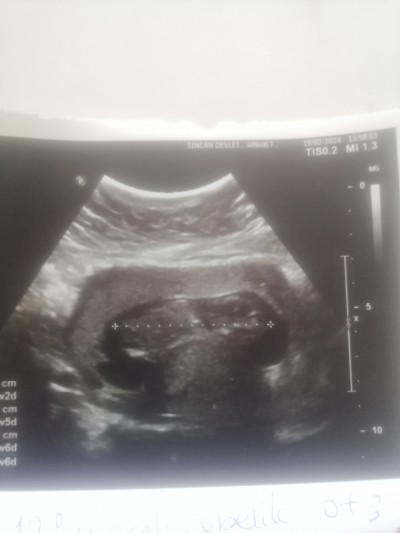

Cinsiyet tahmin

11+5

Neye göre tahmin istiyorsunuz? Hiç bir şey belli değil ki. Ayrıca birazdan kapanır sohbet bölümüne yazın

Kız sohbet bölümüne de doldurmuş 3 tane post açmış ,ama çok bulanık çıkmış keseye göre erkek diyorum ben

Keseden veya yapısından tahmin edebilen vardır belki diye sordum yoksa bizde biliyoruz milletin neye göre yapıp yapamıcağını

Yaa doktor bir tahminde bulundu ama daha çok küçük bişey belli olmaz demişti bende keseden dolayı erkek hissediyorum ama bakalım hayırlısı teşekkür ederim

Detaylı ultrasonu bekle derim Alışveriş için özellikle erken haftalarda yanılma çok oluyor

Canım çok bulanık ama nedense içimden erkek geçti sağlıkla kucağına alırsın inşallah